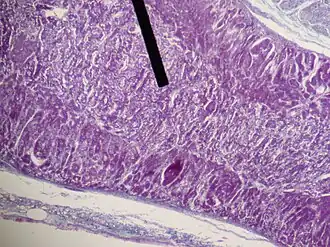

The retinal pigment epithelium (RPE) is a single layer of melanin containing cells located between the neural retina and the choroid. Retinal pigment epithelial cells synthesize dopamine and secrete the neurotrophic factors glial-cell derived neurotrophic factor (GDNF) and brain-derived neurotrophic factor (BDNF).[15] Initial trials of intrastriatal allografts of cultured human retinal pigment epithelial cells attached to microcarriers (Spheramine, Bayer Schering Pharma AG) demonstrated